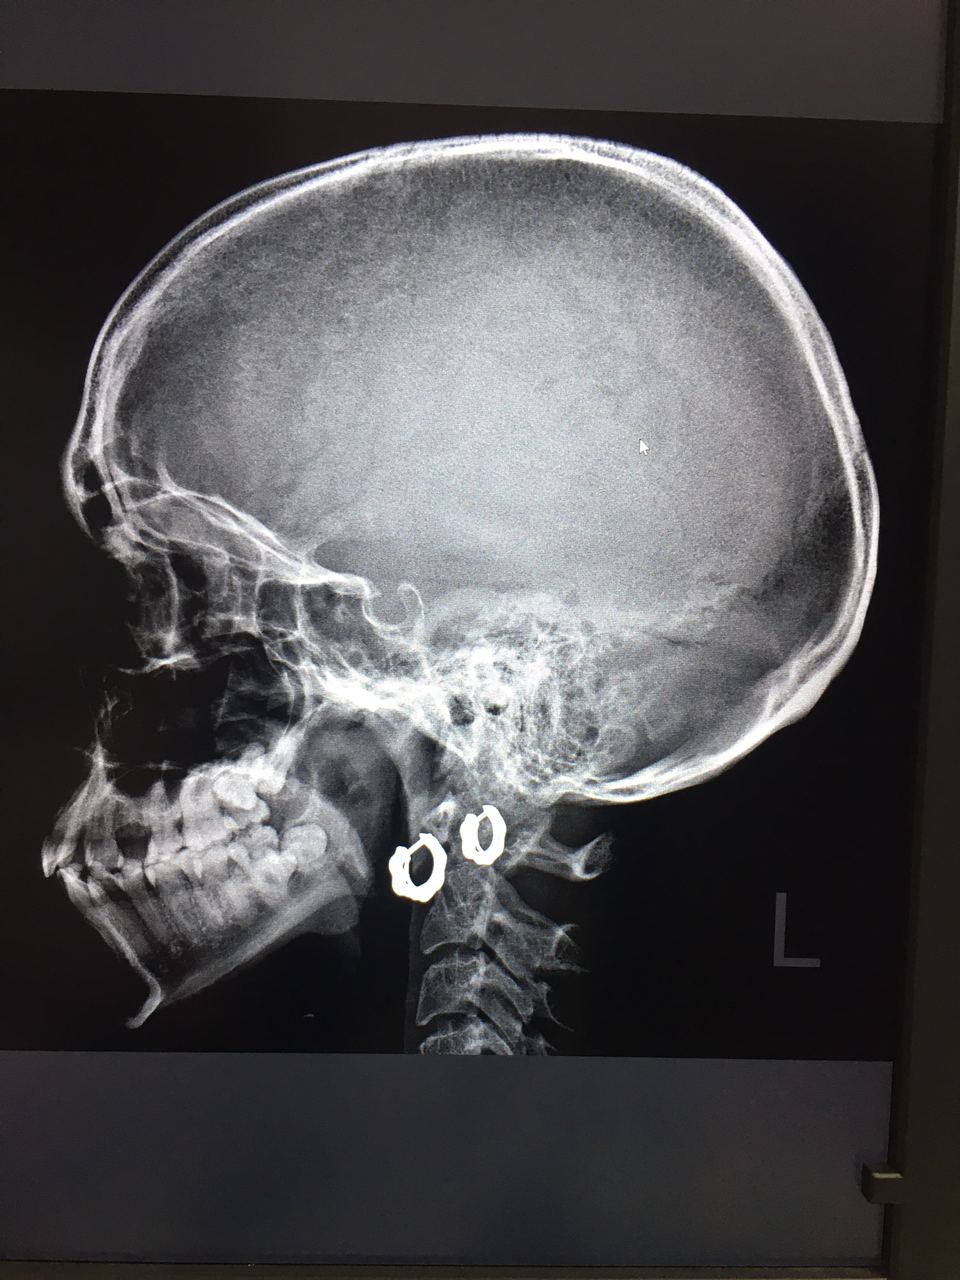

Женщина, 1991 года рождения. В направлении краниалгия.

Никогда до этого череп не приходилось описывать) вроде норма) посмотрите, пожалуйста 😇

А смысл снимать😀

NL

На Мрт

Краниалгия)

Есть ли какие то изменения? Подскажите)

Таня Тимонина

Думаю нет, Мрт в помощь